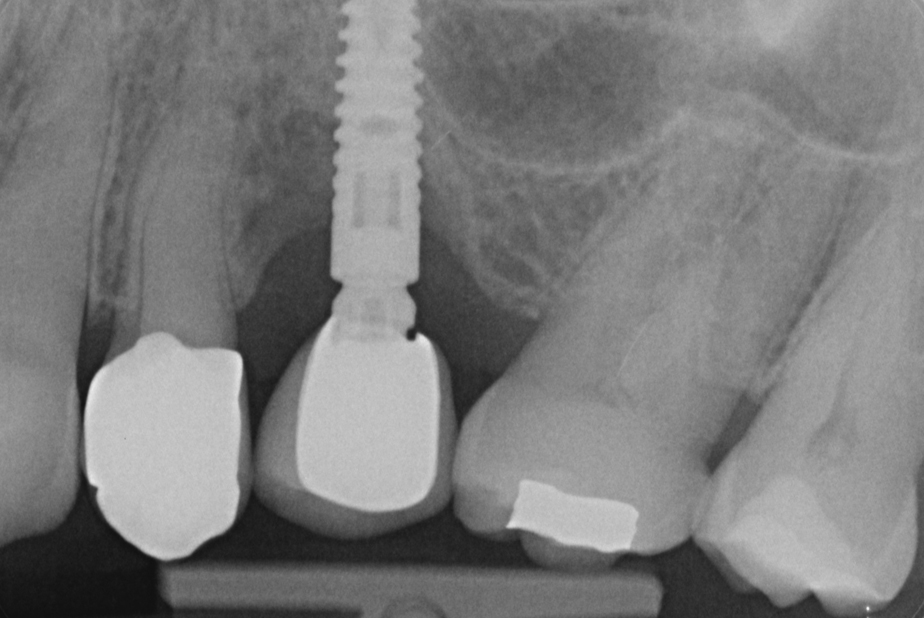

RX al baseline

Fig. 3 - Rx al baseline.

Nell'ultimo anno le è stata riscontrata complicanza a carico dei tessuti peri-implantari di elemento zona 25. L'esame visivo e lo status fotografico (Figs. 1-2) evidenziano un’alterazione dello stato dei tessuti molli peri-implantari, che guida il clinico verso un’indagine più approfondita tramite acquisizione RX. Si esegue perciò esame radiografico del sito coinvolto (Fig. 3), da cui risulta un’importante riassorbimento osseo a carico dell’impianto. Si procede con sondaggio peri-implantare profondo, con la finalità di definire estensione e forma del difetto (Fig. 4) e, associandolo all’esame radiografico, di eseguire la conta delle spire implantari esposte. Tale manovra verrà effettuata con l’impiego di anestetico da irrigazione, data la nota dolorolabilità in peri-implantite, in quanto tale patologia determina la perdita di barriere connettivali e pertanto la penetrazione in osso durante il sondaggio.